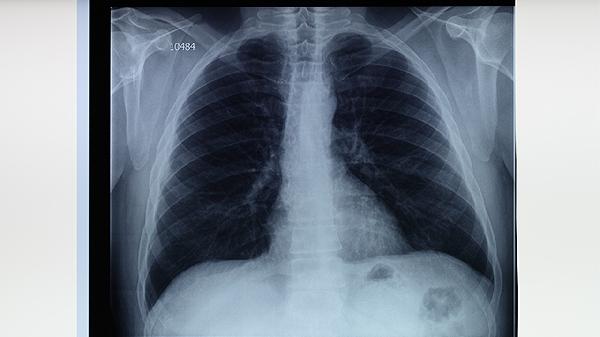

对于耐药性肺结核或药物不良反应严重的患者,中医辨证施治能减轻肝损伤、胃肠不适等副作用。针灸、艾灸等传统疗法也可辅助改善体质,但所有中医干预都应在抗结核治疗基础上进行。肺结核患者必须完成6-9个月的规范西药疗程,定期复查痰菌和胸部影像学变化。

肺结核患者需保持均衡饮食,适量摄入优质蛋白和维生素A/C/D。避免辛辣刺激食物,戒烟限酒,保证充足睡眠。居住环境应通风良好,佩戴口罩防止飞沫传播。出现咯血、持续发热等症状时须立即就医,不可自行停用抗结核药物或单纯依赖中医治疗。